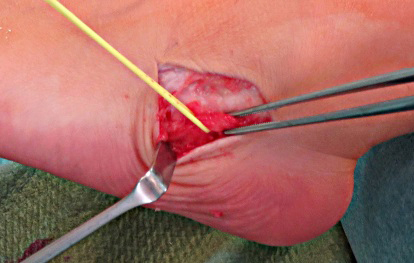

• Hautschnitt: Von der Außenknöchelspitze bis über den Sinus tarsi, ggf. distal etwas nach dorsal auslaufend. (Bild 6,7)

• Darstellen und ggf. Anschlingung des N. suralis. (Bild 8a)

• Inzision des Sinus tarsi unter der Schutz der Peronaealsehnen und der N. suralis. (Bild 8b,9,10)

• Präparation des Fettkörpers gemeinsam mit der Ablösung des Ansatzes des Extensor digitorum brevis nach distal und Anschlingung. Auf Erhalt der Innervation ist zu achten. (Bild 11)

• Vervollständigung der Ausräumung des Sinus tarsi mit dem Luer. (Bild 12)

• Mit dem Meißel wird eine Rinne von 4-5mm Breite bis in die Spongiosa angelegt am Unterrand des Talus direkt vor der hinteren Facette (Dach des Sinus tarsi) (Bild 13) und am Oberrand des Kalkaneus (Boden des Sinus tarsi) (Bild 14). Die laterale Kortikalis sollte geschont werden, der Span soll bei in 0-Stellung stehendem Fuß in Verlängerung der Tibia stehen.

• Mit dem stupfen Ende verschieden breiter Lambotte-Meißeln wird die geeignete Spangröße ermittelt mit der der Rückfuß korrigiert ist (Bild 15). Eine Überkorrektur in den Fersenvarus ist zu vermeiden. Der Span wir in der Regel trapezförmig zugeschnitten

• Einbringen des Spanes mit der Basis nach Lateral und einstößeln. (Bild 16) Überprüfen der Korrektur (Bild 17)

• Stabilisierung des Spanes mit Kirschnerdrähten (Bild 18).

• Drainage, Verschluss des Sinus tarsi mit dem angeschlungenen Fascien-Sehnenlappen (Bild 19,20).